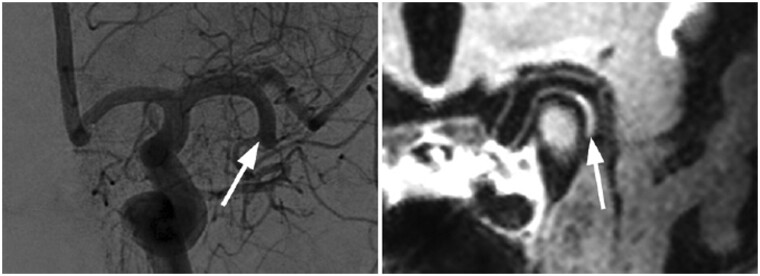

Abstract Image